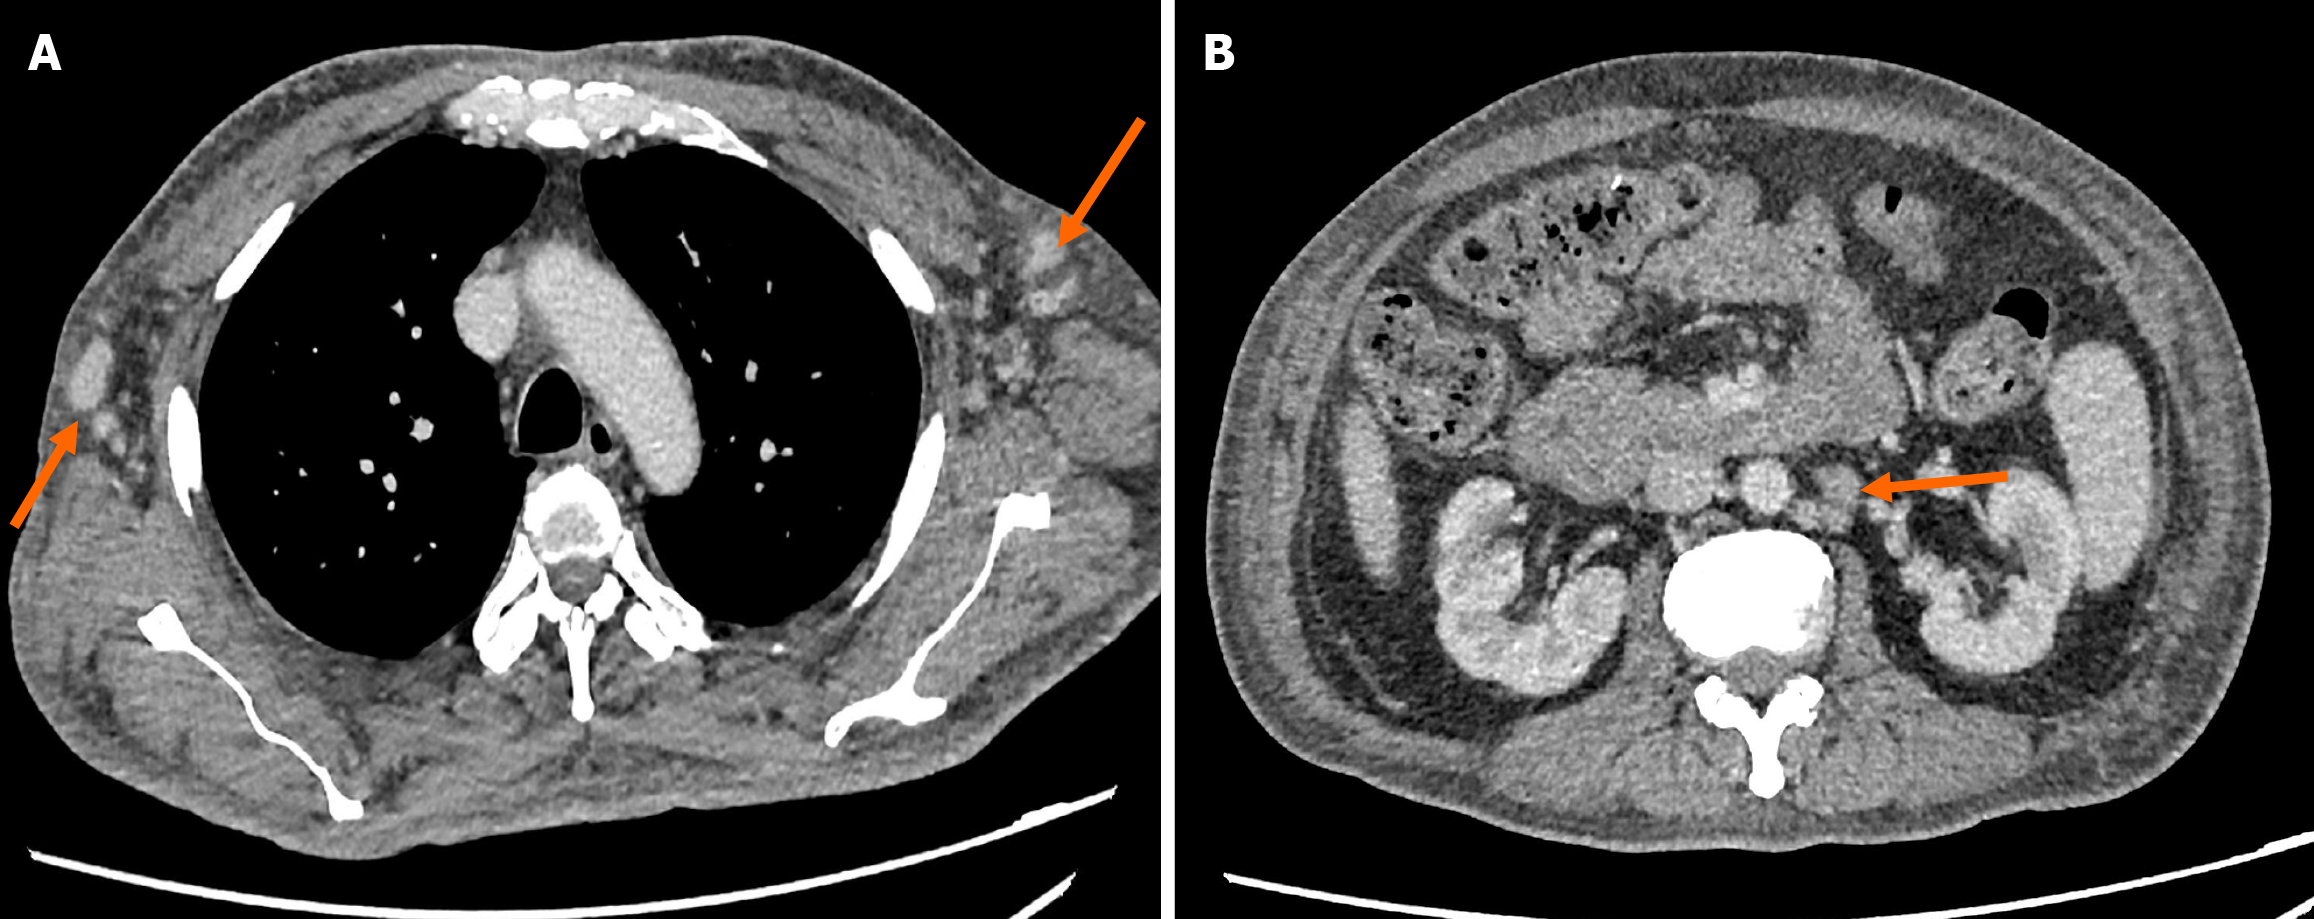

Figure 6 Contrast enhanced computed tomography thorax and abdomen.

A: Axial view depicting enlarged lymph nodes at bilateral axillary region (arrows); B: Axial view at abdominal level showing lymphadenopathy at paraaortic region (arrow).